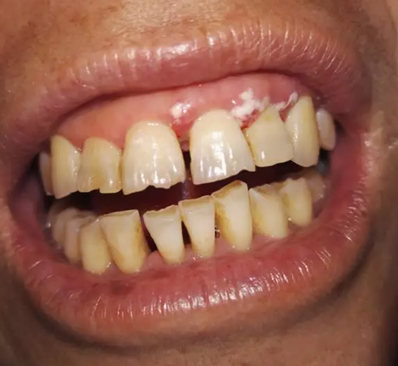

該患者本身就有慢性牙周炎,加上高血壓的基礎(chǔ)疾病,長期服用硝苯地平,這個是導致藥物性牙齦增生常見藥物之一,針對這樣的患者在牙周基礎(chǔ)治療時必要的,但在基礎(chǔ)治療的同時,一定要建議患者更改降壓藥物,同時必要時手術(shù)切除增生牙齦,可以達到很好的效果,見圖片(圖中白色為雙氧水沖洗后效果)。